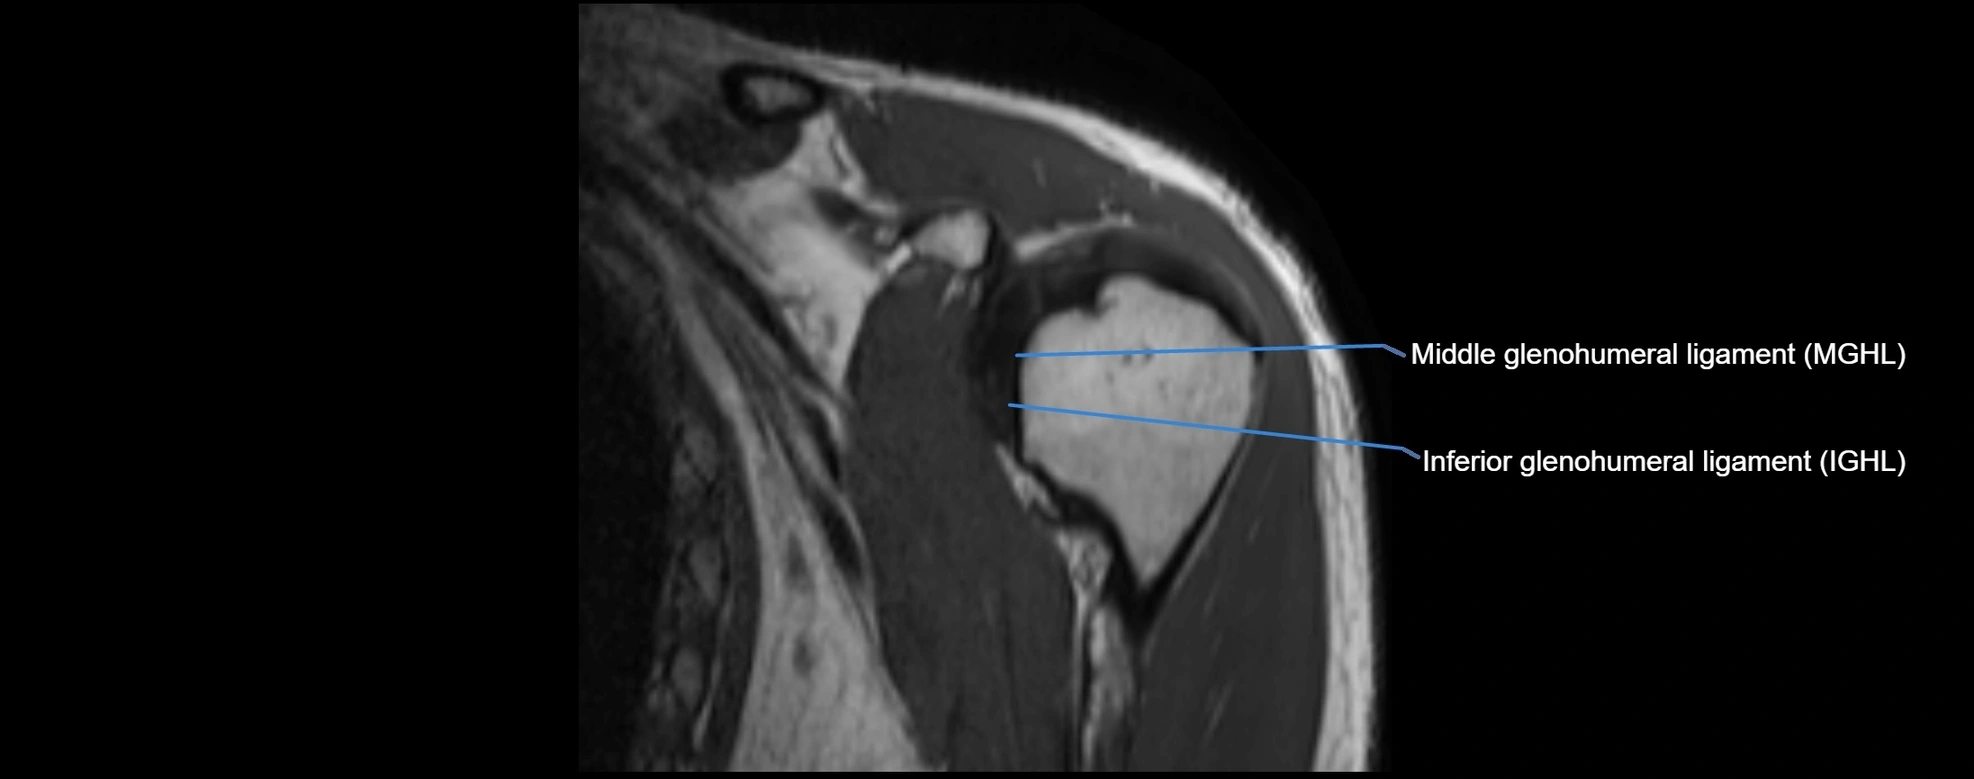

MRI images

image